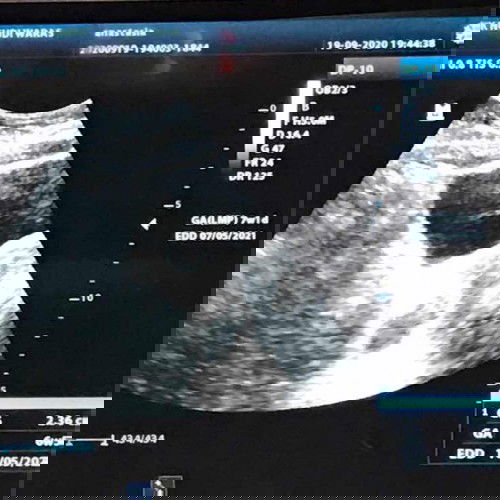

Mengulang usg diklinik karna janin tidak terlihat saat usg di rs

Saya ada riwayat BO bun kmrin usia 10w harus kuret, kosong 7minggu lalu isi lagi saat ini usia kandungan ke dua memasuki 7w td siang saya ke rs waktu di usg hanya terlihat kantong dan janin hanya berbayang tidak jelas, karna saya trauma BO malamnya saya usg lagi namun ke klinik bun, bahagia bngt liat ada titik didalam kantong, walau tidak jelas... namun itu membuat saya bernafas lega